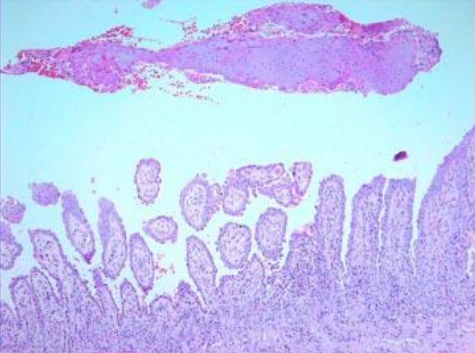

This patient comes to your clinic with onycholysis and Auspitz sign. What observations in this slide help you confirm that the patient has psoriasis?

Hyperkeratosis, parakaratosis, acanthosis, Rete ridges, Munro micro abscess (collection of neutrophils) and thinning of the epidermis over the dermal papilla.